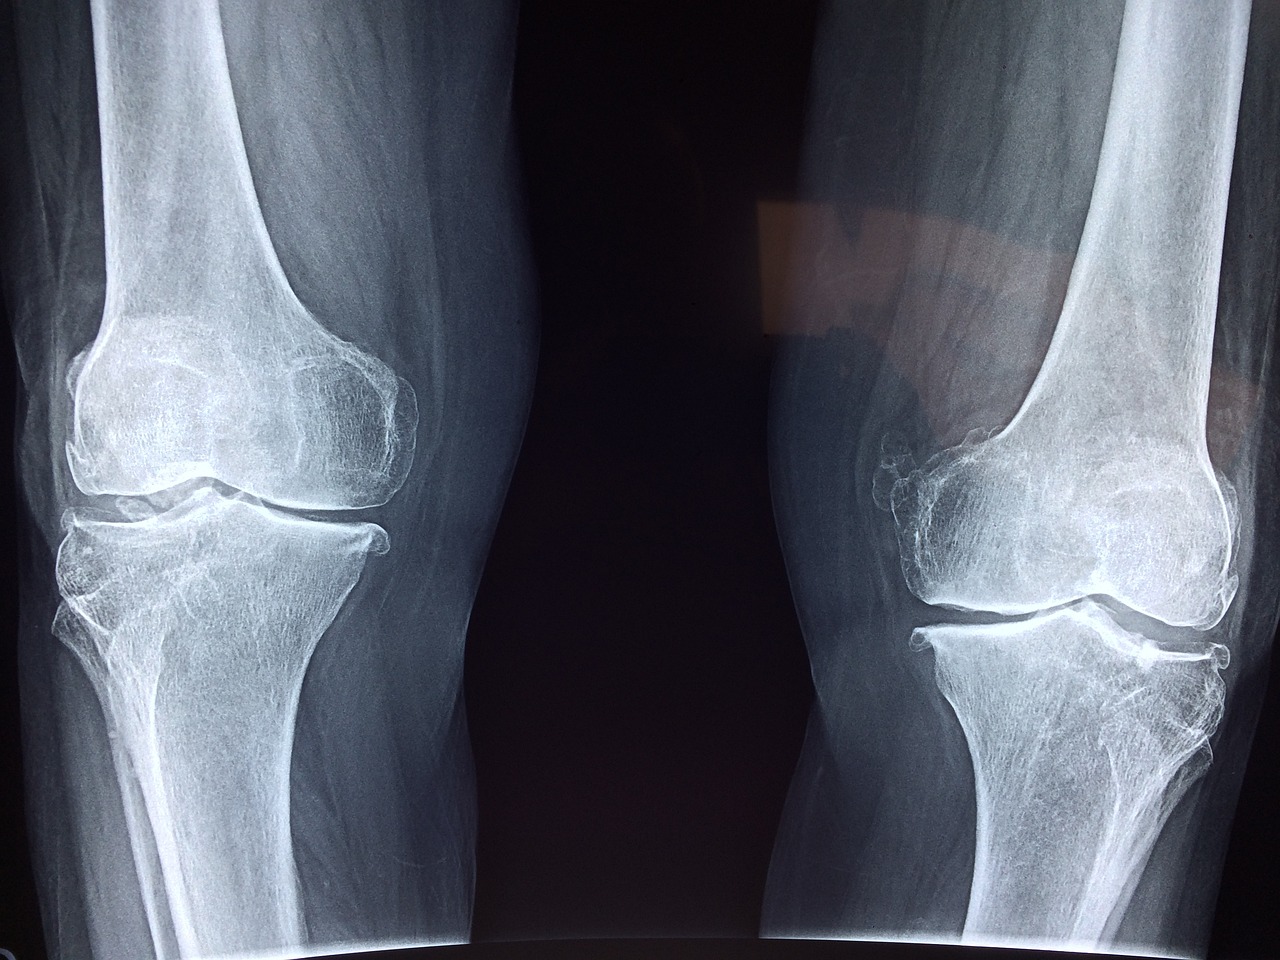

무릎 인공관절 수술을 받은 후, 다리를 제대로 굽히고 펴는 것이 왜 이렇게 어려울까요?

많은 분들이 수술 후 무릎 인공관절 각도가 어느 정도여야 정상인지, 또 회복 과정에서 어떤 기준을 참고해야 하는지 궁금해하십니다.

특히 인공관절 수술 후 무릎의 굽힘 각도(flexion)와 폄 각도(extension)는 일상생활 복귀에 있어 매우 중요한 지표입니다. 각도가 충분하지 않으면 걷기, 계단 오르내리기, 심지어 앉기조차 어려워질 수 있기 때문입니다. 무릎 인공관절 각도에 대한 기준, 회복 과정에서의 목표치, 그리고 재활 팁까지 함께 알아볼까요?

1️⃣ 무릎 인공관절 각도란 무엇인가요?

✅ 무릎 인공관절 각도란?

● 무릎 인공관절 각도는 무릎을 얼마나 굽히고 펼 수 있는지를 수치로 나타낸 것입니다.

● 일반적으로 병원에서는 무릎 굽힘 각도와 폄 각도를 각각 측정하여 회복 상태를 판단합니다.

● 굽힘 각도는 다리를 최대한 접었을 때의 각도이며, 폄 각도는 다리를 곧게 펴는 정도를 의미합니다.